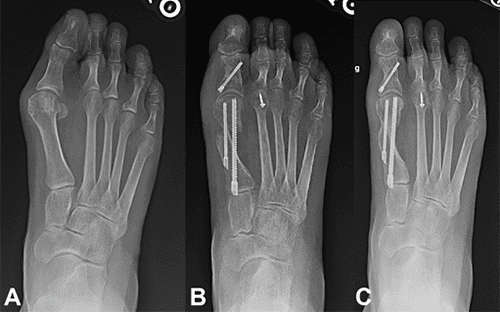

Bunion surgery isn’t a one-size-fits-all solution. In Australia, patients have access to a variety of surgical techniques, each tailored to suit different levels of deformity, patient lifestyle, and individual anatomy. The key to achieving the best outcome lies in thorough consultation with a qualified podiatric or orthopaedic surgeon. They’ll assess your condition, review imaging (such as X-rays), and discuss your personal goals and expectations.